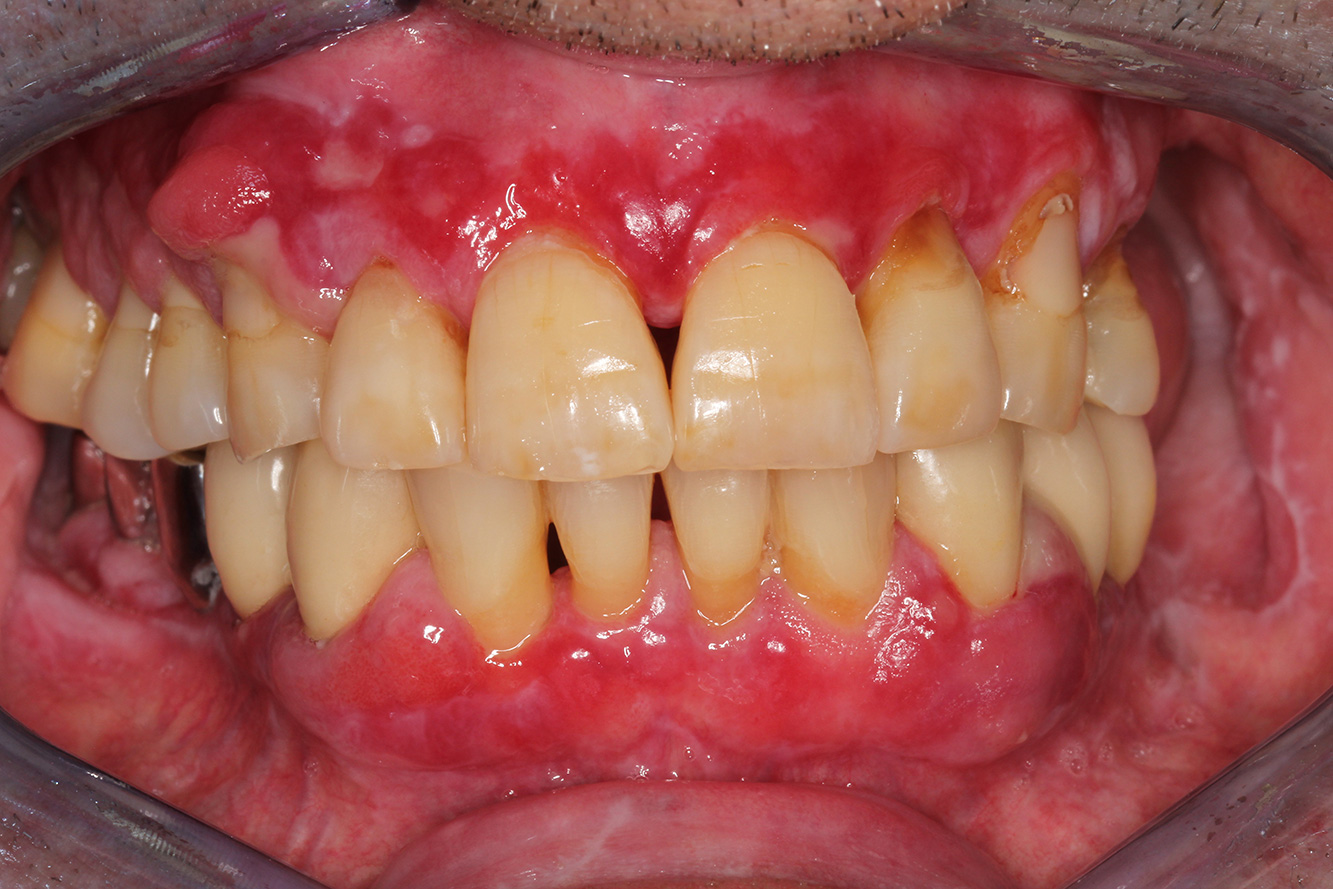

Se presenta un paciente de 71 años con trasplante de riñón e hipertensión (presión arterial alta). Debido a su historia médica, es necesario el tratamiento continuo con ciclosporina para suprimir el sistema inmunitario y amlopidina para bajar la presión arterial. Además, el paciente relata encías sensibles y sangrantes. Desde el punto de vista de la salud oral, hay dientes restaurados con ocho piezas faltantes, hiperplasia gingival pronunciada, periodontitis en fase II, de grado B con bolsas activas y una caries inicial en la pieza 22. En la evaluación del riesgo de caries se ha establecido un riesgo de caries medio (API 60). Para la sesión de profilaxis se hacen las siguientes recomendaciones.

Con base en la historia médica, se detecta un riesgo de complicaciones importante. Debido al trasplante de riñón, el paciente está inmunodeprimido (ciclosporina), también tiene el sistema inmunitario debilitado y necesita profilaxis para infecciones (recomendación: 2 g de amoxicilina como antibiótico 1 h antes de la sesión). Al mismo tiempo, el tratamiento continuo hace que el paciente tenga un mayor riesgo de enfermedad, dado que la hiperplasia gingival establecida está asociada a la medicación (20).

Se debe abordar la situación del paciente, especialmente cuando se trata de motivación y aprendizaje. La hiperplasia gingival dificulta la higiene oral en casa. La mayor susceptibilidad a las infecciones y el progreso y la nueva formación de hiperplasias (22) debe hablarse de igual a igual. Al mismo tiempo, deben explicarse las técnicas de higiene adecuadas según las necesidades individuales.

Para el paciente se recomienda un intervalo de control posterior más corto, de tres a cuatro meses. Esto se debe principalmente a la hiperplasia gingival asociada a la medicación, la situación de cuidado difícil asociada y el alto riesgo de progresión de la periodontitis.